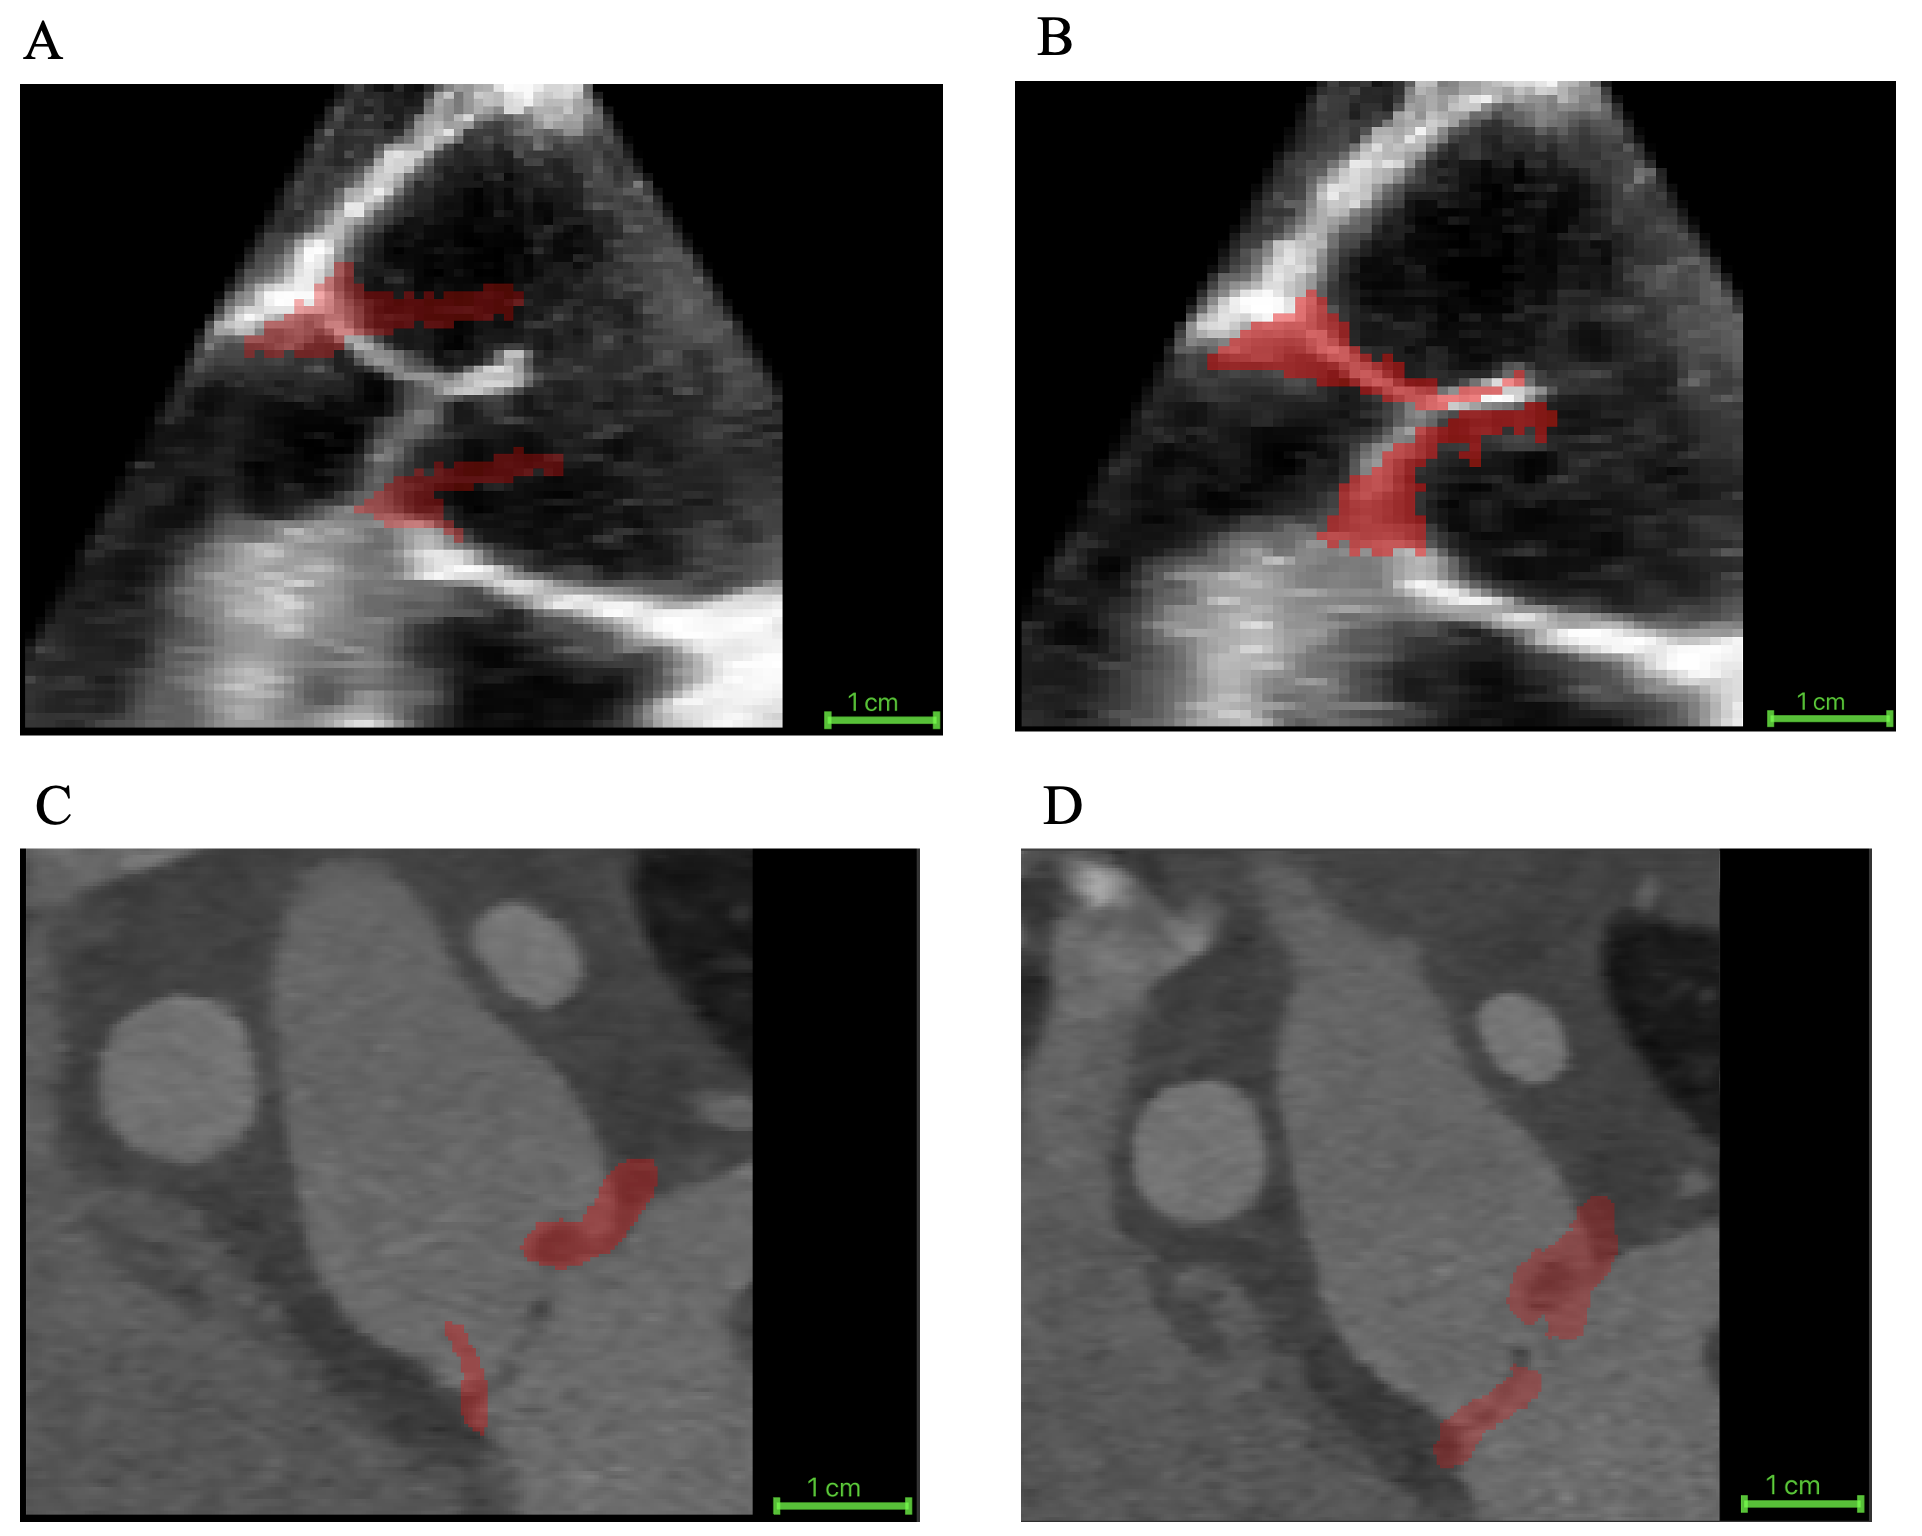

The proposed biomechanically informed registration improved segmentation-tracking accuracy by an average of 40%, reflecting the reduction in the mean distance between the tracked closed-state segmentation and the manual ground truth across all 20 cases when compared with direct registration. Specifically, this mean distance decreased from 3.70 ± 2.30 mm with direct registration (no FEM) to 2.23 ± 1.27 mm using our approach. Table 3 summarizes registration accuracy across valve morphologies and imaging modalities, comparing the mean distance between the manual ground truth and the propagated segmentation obtained with direct registration and proposed FEM-augmented registration. Figure 3 illustrates an example of the reconstructed patient-specific aortic valve closure (shown in red) overlaid on mid-diastole grayscale images. Panels A and B show a TEE case, and panels C and D show a CT case. For each modality, the left panel displays the result from direct registration, and the right panel shows the result from the FEM-augmented registration method. Furthermore, to assess the biomechanical behavior of different valve morphologies, we evaluated leaflet strain in adult trileaflet, adult bicuspid, and pediatric cases and compared the resulting strain ranges. The resulting strain maps exhibited physiologically consistent patterns.

Refer to caption

Figure 3: Example of image-based registration results for one TEE case and one CT case. The reconstructed aortic valve leaflets at mid-diastole are shown in red. (A) TEE with direct registration, (B) TEE with FEM-augmented registration, (C) CT with direct registration, and (D) CT with FEM-augmented registration.